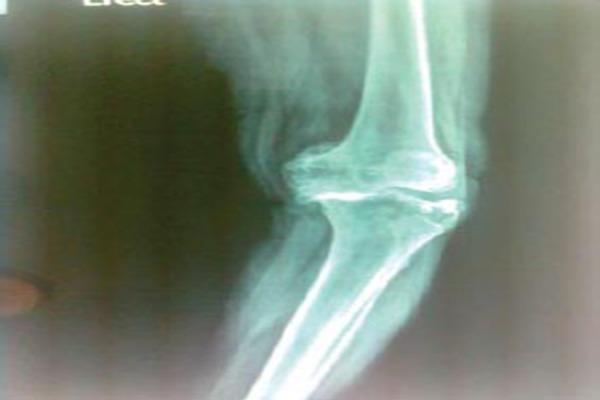

A 70yrs old Female was admitted in our institution diagnosed with severe bilateral Osteoarthritis. The x-rays showed bone on bone Tricompartment OA Knee with Varus Malalignment. She was posted for Single Stage Bilateral Total Knee Replacement and as planned the Left Knee Was Operated first. After exposure, Proximal Tibial, Distal Femoral Cuts and measurement of extension gaps the synovium from the anterior Femur was removed and sizing was done. The AP cut was then proceeded with. We spotted a small Osteochondral Cyst in the Anterior Femur which was curretted to remove the cystic material, which is when we realised that the cyst was large and communicating with the medulary canal. The remaining Femoral preparations was done keeping in mind the risk of iatrogenic fracture and extension Stem was used in the femur. The defect was then packed cancellous bone graft.

一名70岁女性因双侧严重骨关节炎入住我院。X线显示三关节骨对骨的膝关节骨关节炎伴内翻畸形。她计划接受一期双侧全膝关节置换术,按计划先对左膝进行手术。暴露后,进行胫骨近端、股骨远端截骨并测量伸直间隙,切除股骨前部的滑膜并进行尺寸测量。然后进行前后位截骨。我们在股骨前部发现一个小的骨软骨囊肿,将其刮除以去除囊肿内容物,此时我们意识到囊肿很大且与髓腔相通。在考虑到医源性骨折风险的情况下完成剩余的股骨准备工作,并在股骨中使用延长柄。然后用松质骨移植填充缺损。